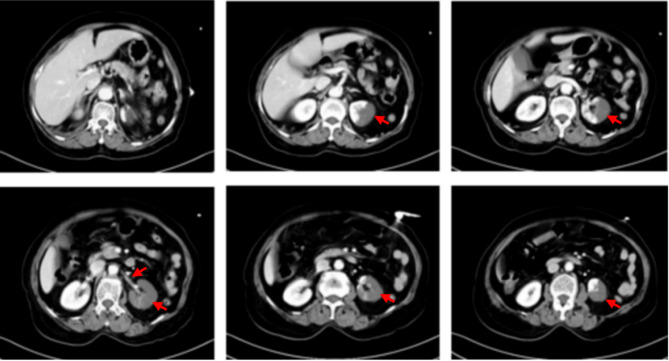

Results: The diagnostic checklist was organized into five principal etiological categories: local organ disorders, diseases of adjacent organs, systemic diseases, psychogenic disorders, and gynecological conditions. Its implementation facilitated the accurate identification of atypical acute renal infarction in a diagnostically challenging case, enabling prompt clinical intervention.